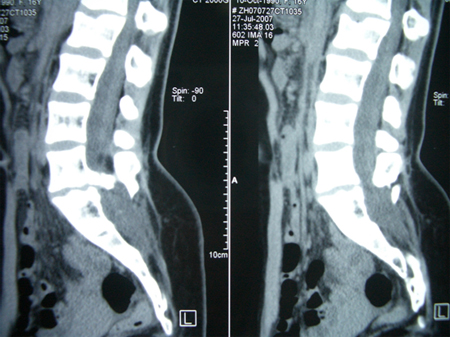

术中发现L4-5椎板异常增生肥厚,L5椎板伸入椎管内形成骨嵴,脊髓圆锥低位在L4水平,L4以下肿瘤组织为多种成份,近端为脂肪组织,S1水平分为两种肿瘤成份,内侧为清亮粘液状物、外侧为珍珠样角化物。

专家评点:有骨性分割的脊髓拴系,因在咬除骨性分隔时,常挤压脊髓结构,所以术后常有一过性神经功能障碍加重,应以激素冲击和甘露醇脱水治疗。